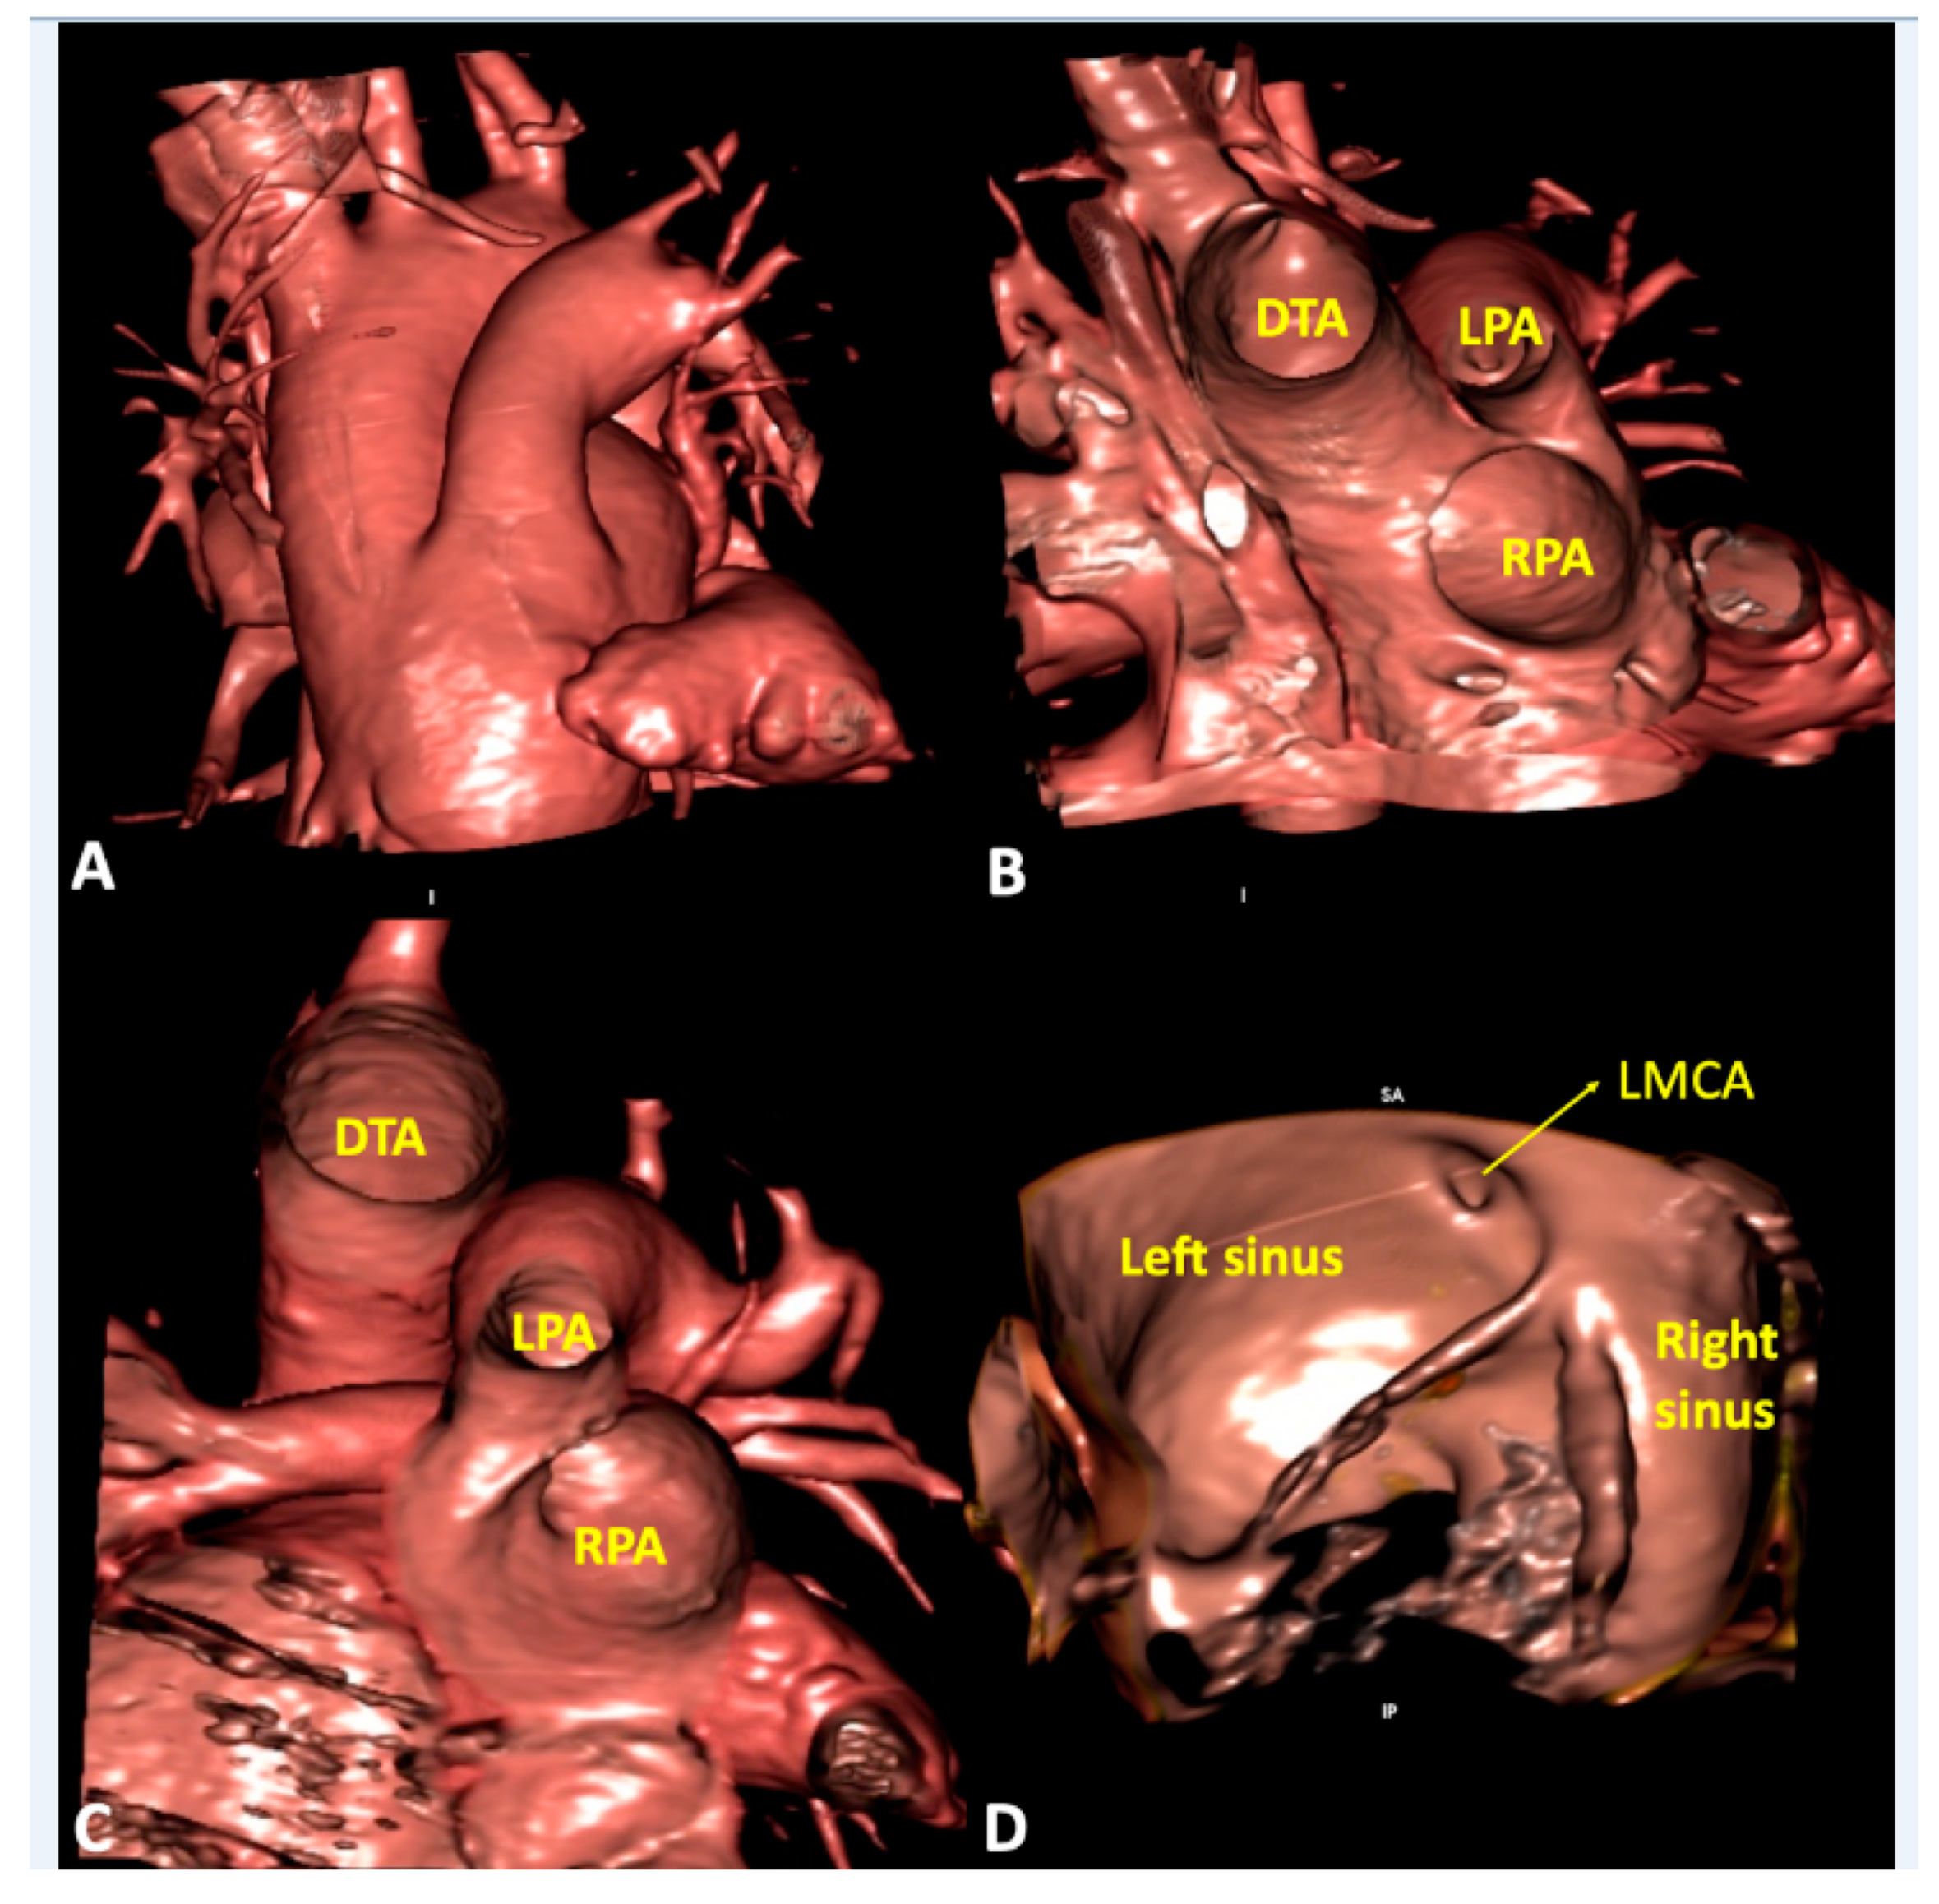

5. Clinical Implication in Acquired Heart Disease with Representative Cases

6. Clinical Implication in Congenital Heart Disease with Representative Cases